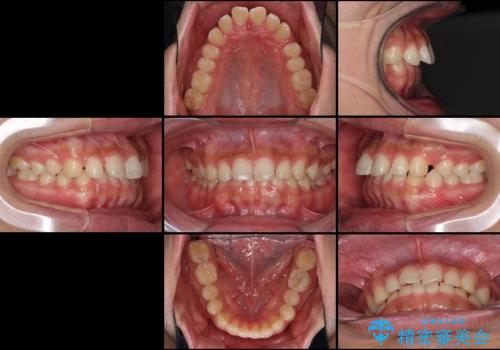

インビザラインによる、すきっ歯の改善

- 前歯がすきっ歯であることを気にして来院された患者様です。

下の前歯がほとんど隠れてしまうくらいの深い咬み合わせであったので、インビザラインを用いて、咬み合わせの高さを改善しながら隙間を閉じていくこととしました。

咬合力で上の前歯が前方に押し出されるようにして隙間ができていましたが、矯正治療により全て閉じることができました。

深い咬み合わせも多少改善され、隙間も閉じたことで、前方に出ていた前歯が引っ込んだため、口も閉じやすくなったとのことでした。